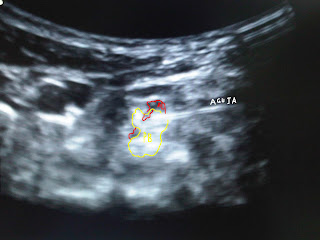

En la muñeca, el nervio cubital pasa lateral al hueso pisiforme y medial al hueso ganchoso en una zona conocida como el canal de Guyon. La arteria cubital esta antero lateral al nervio a este nivel da inervación motora al musculo cubital anterior y al flexor común profundo de los dedos, en la mano inerva todos los músculos que están situados por debajo y por dentro del tendón flexor largo del pulgar y no emite ramas sensitivas del antebrazo, suele inervar la piel del dedo meñique y la mitad interna de la mano y del dedo anular